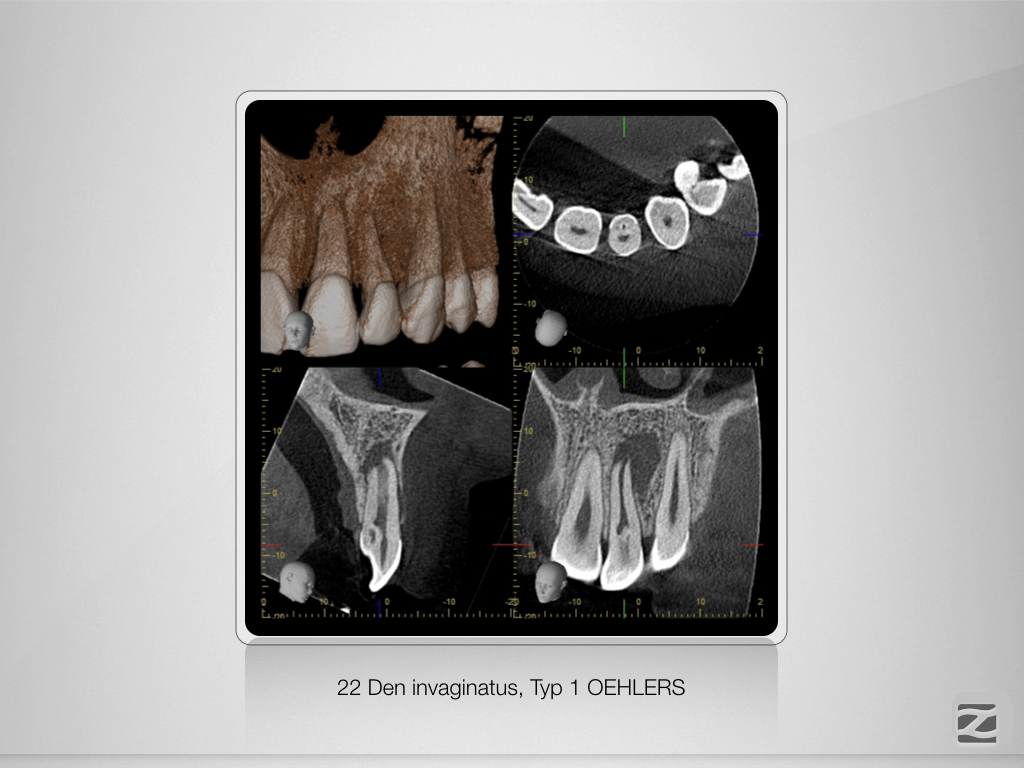

Dens invaginatus